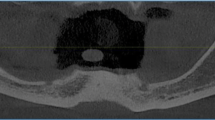

Three 2.4-mm screws were placed to demarcate the anterior midline and posterior lateral lines on each side of the model. Computer-aided design/computer-aided manufacturing (CAD-CAM) wax (MarmoScan; Siladent, Goslar, Germany) was used to cover the screw heads and facilitate recognition during optical scanning (Fig. 2). We utilized a high-resolution cone-beam computed tomography machine (Planmeca Promax 3D Mid Dental Volumetric Tomography, Helsinki, Finland) to perform the CBCT scans. These scans were carried out using the subsequent parameters: 90 kV, 10 mA, and 36 s, with a Field of View (FOV) of 16 × 9 cm. White CAD-CAM spray (Dr. Mat, Istanbul, Turkey) was applied to the models to obtain higher-quality scans. The scanned gingival surface texture was transferred to the software of the NeWay optical 3D scanner (Open Technologies, Rezzato, Italy) (Fig. 3).

During the interventions, the models were firmly fastened in a vise and stationed on a table to ensure stability and diminish variability throughout the procedure. A single operator performed all interventions, an accomplished oral surgeon with a track record exceeding ten years in the field of implant placement. The aim behind this was to mitigate any operator-dependent factors that could possibly affect the precision of implant placement. Surgical guides were fixed to the models using three pins passed through the sleeves (1.3 × 28 mm). The implants were placed in accordance with the recommended surgical protocol. Following implant placement, CBCT scans of the models were obtained. DICOM data were used to assess deviations from the planned locations. Marker screws were used for superimposition. The comparison module of the coDiagnostiX software was used for the assessment. Positional accuracy was evaluated by comparing the virtually planned and actual implant positions (Fig. 4). The implant placement accuracy was assessed based on angular deviations at the base [angle (A), 3D offset (B3D), distal (BD), vestibular (BV), and apical (BA)] and tip [3D offset (A3D), distal (AD), vestibular (AV), and apical (AA)].